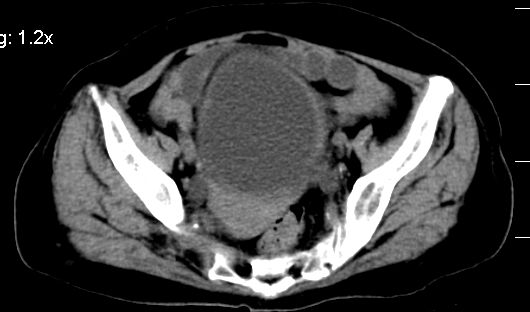

标题: CT10133:F、74岁,反复血尿10天。 [打印本页]

标题: CT10133:F、74岁,反复血尿10天。

膀胱三角区不规整软组织改变,双侧输尿管扩张,所以占位性病变肯定首先考虑,建议改变体位扫描除外游离血块影,但老年人出血原因一定要查明。

1.膀胱后壁见不规则致密影,随体位改变,为膀胱内凝血块;

2.双侧输尿管下段扩张.输屎管结石可能大。建议作进一步检查。

2.双侧输尿管下段扩张.输屎管结石可能大。

双侧输尿管下端扩张,并膀胱内血凝块 输尿管下端结石

2.双侧输尿管下段扩张,临床有血尿病史,建议进一步检查,找出血原因。